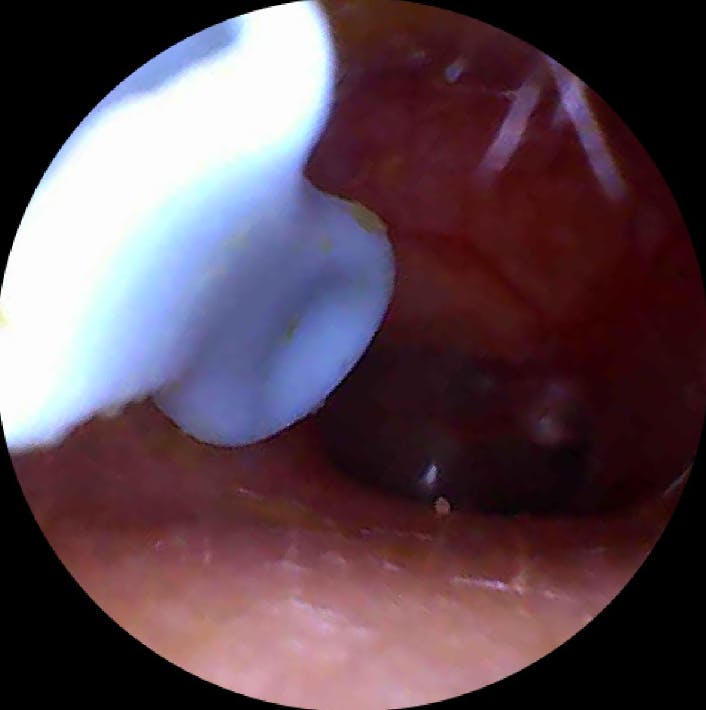

Ich bin wirklich überraschend begeistert von diesem Ohrenendoskop. Die Handhabung ist kinderleicht, die Verbindung zum Smartphone hat auf Anhieb funktioniert und die Bildqualität ist überraschend gut – gestochen scharf und detailreich. So konnte ich mir das Ohrinneres problemlos anschauen und erkennen, was los ist.

Besonders praktisch finde ich das schlanke Design und die integrierte Beleuchtung – dadurch sieht man selbst kleine Details sehr klar. Auch die mitgelieferten Aufsätze und Werkzeuge sind gut verarbeitet und machen die Anwendung noch einfacher und hygienischer.

Mit diesel Gerät kann ich selbst in regelmäßigen Abständen das Ohr vom gröbsten Ohrenschmalz befreien. Mit diesem Gerät tut es überhaupt nicht weh, die Aufnahmen der Kamera sind sehr gut. Mit etwas Geduld, Übung und Vorsicht kann man das Ohr wirklich sehr gut reinigen, ohne es zu verletzen. Ich kann das Produkt ohne Vorbehalte weiterempfehlen und würde es wieder kaufen.

Hier findest du echte Kundenmeinungen über den Miluna™ Pro – den beliebten visuellen Ohrenreiniger mit HD-Kamera, LED-Beleuchtung und sanften CleanScoop™-Aufsätzen. Bereits über 40.000 Kund:innen aus dem deutschsprachigen Raum haben unsere Ohrenreinigungslösung getestet und teilen auf dieser Seite ihre ehrlichen Erfahrungen – von der einfachen Anwendung bis zum Ergebnis nach der Reinigung.